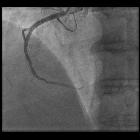

DSA technique

Digital subtraction angiography is used to produce images of the blood vessels without interfering shadows from overlapping tissues. This provides a clear view of the vessels and allows for a lower dose of contrast medium .

- the non-contrast image (mask image) of the region is taken before injecting contrast material and therefore shows only anatomy, as well as any radiopaque foreign bodies (surgical clips, stents, etc.) as would a regular x-ray image.

- contrast images are taken in succession while contrast material is being injected. These images show the opacified vessels superimposed on the anatomy and are stored on the computer.

- the mask image is then subtracted from the contrast images pixel by pixel. The resulting subtraction images show the filled vessels only.

- recording can continue to provide a sequence of subtracted images based on the initial mask.

- the subtraction images can be viewed in real-time. Even if the patient lies still, there is bound to be some degree of misregistration of images due to movement between the acquisition of the mask image and the subsequent contrast images. The effect is prominent at high-contrast interfaces, such as bone-soft tissue, metal staples and coils, and bowel air. Pixel shifting (either manual or automatic), i.e. moving the mask retrospectively, can minimize misregistration, but focal movement such as bowel peristalsis, will not be corrected.